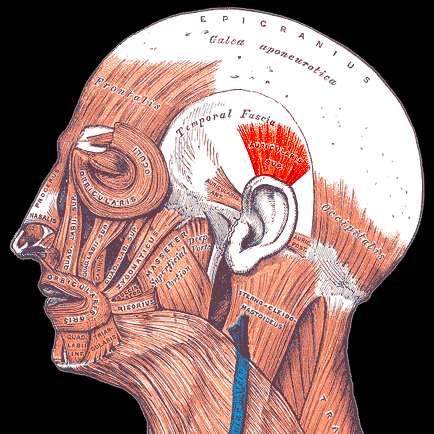

Ականջների մկաններ